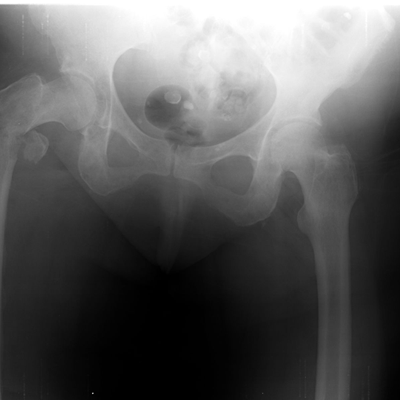

X-rays are primarily used in the medical and dental field. Some of the more common X-rays are done for broken bones and fractures, swallowed items, damage to bones from arthritis, and lung infections. X-rays are also used in a CT scanner, or computed tomography. This modality uses multiple X-rays during one scan, to give a layer-by-layer image. X-rays are also being used in non-medical areas, like airport security and by NASA in outer space.